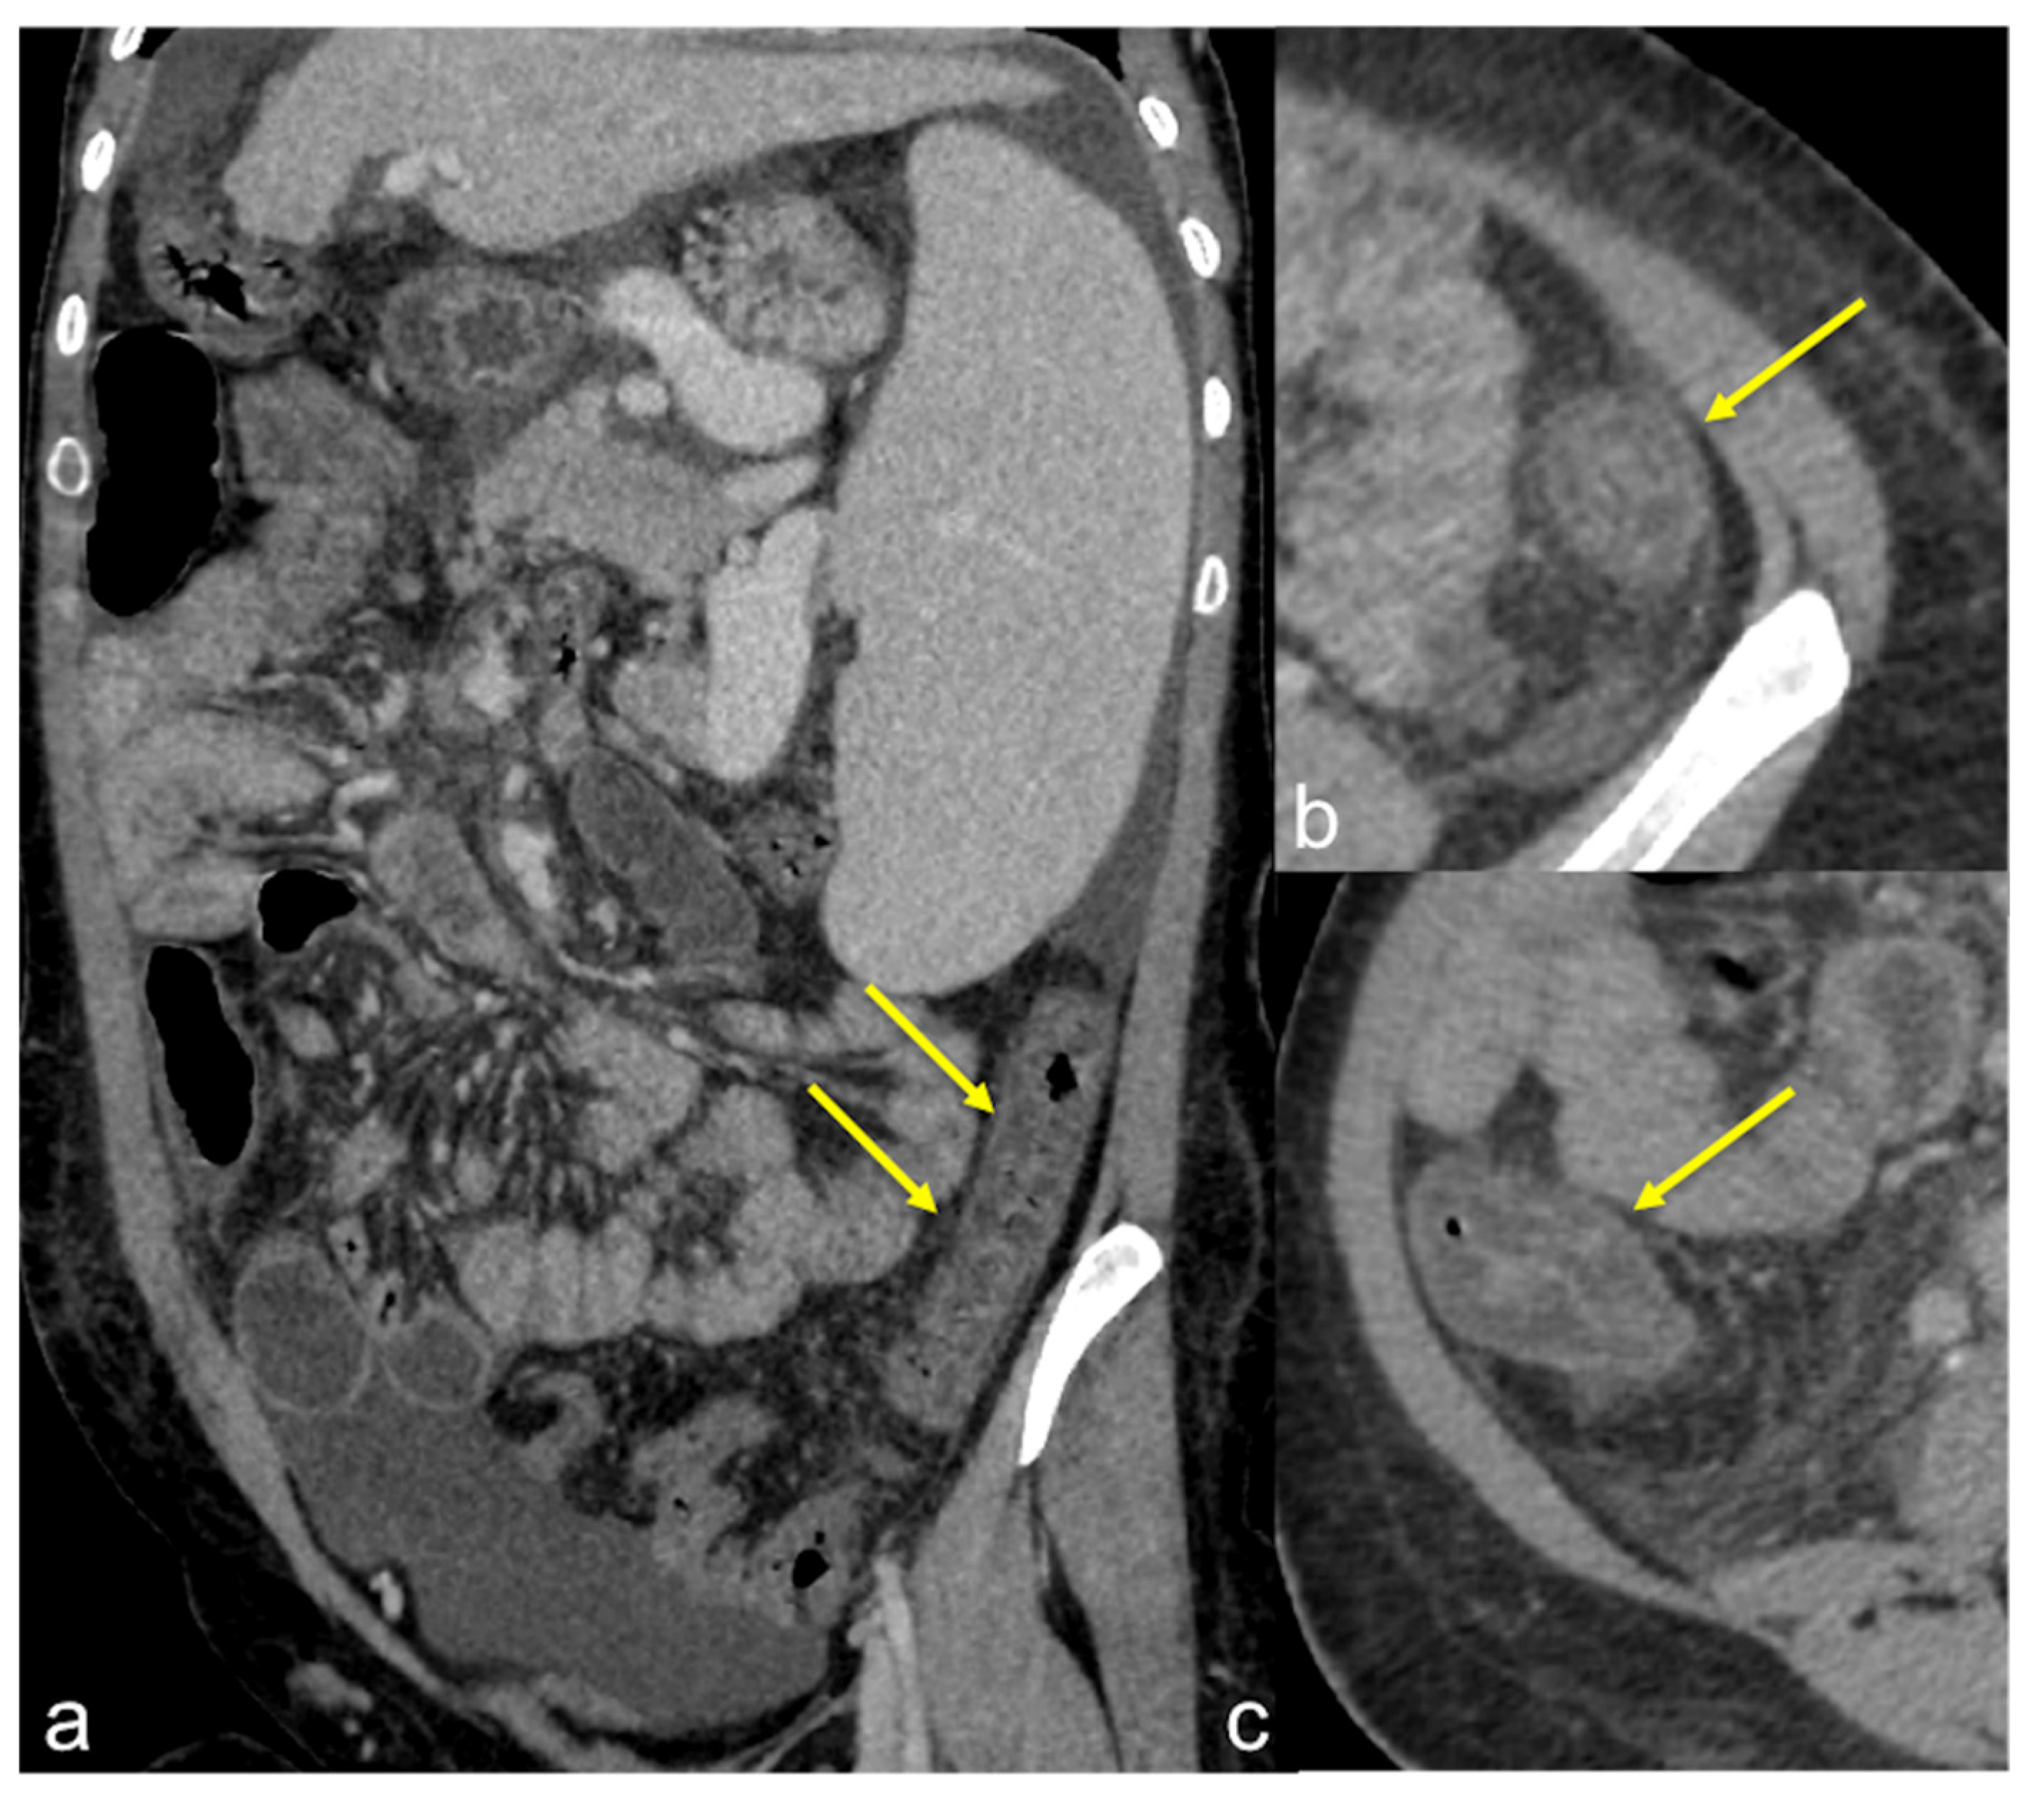

| Aorto-Enteric Fistula (Figure 31) | Bleeding in a patient with a history of surgery for aortic aneurysm. | A connection between the aorta and the intestinal lumen. Absence of adipose cleavage planes. |